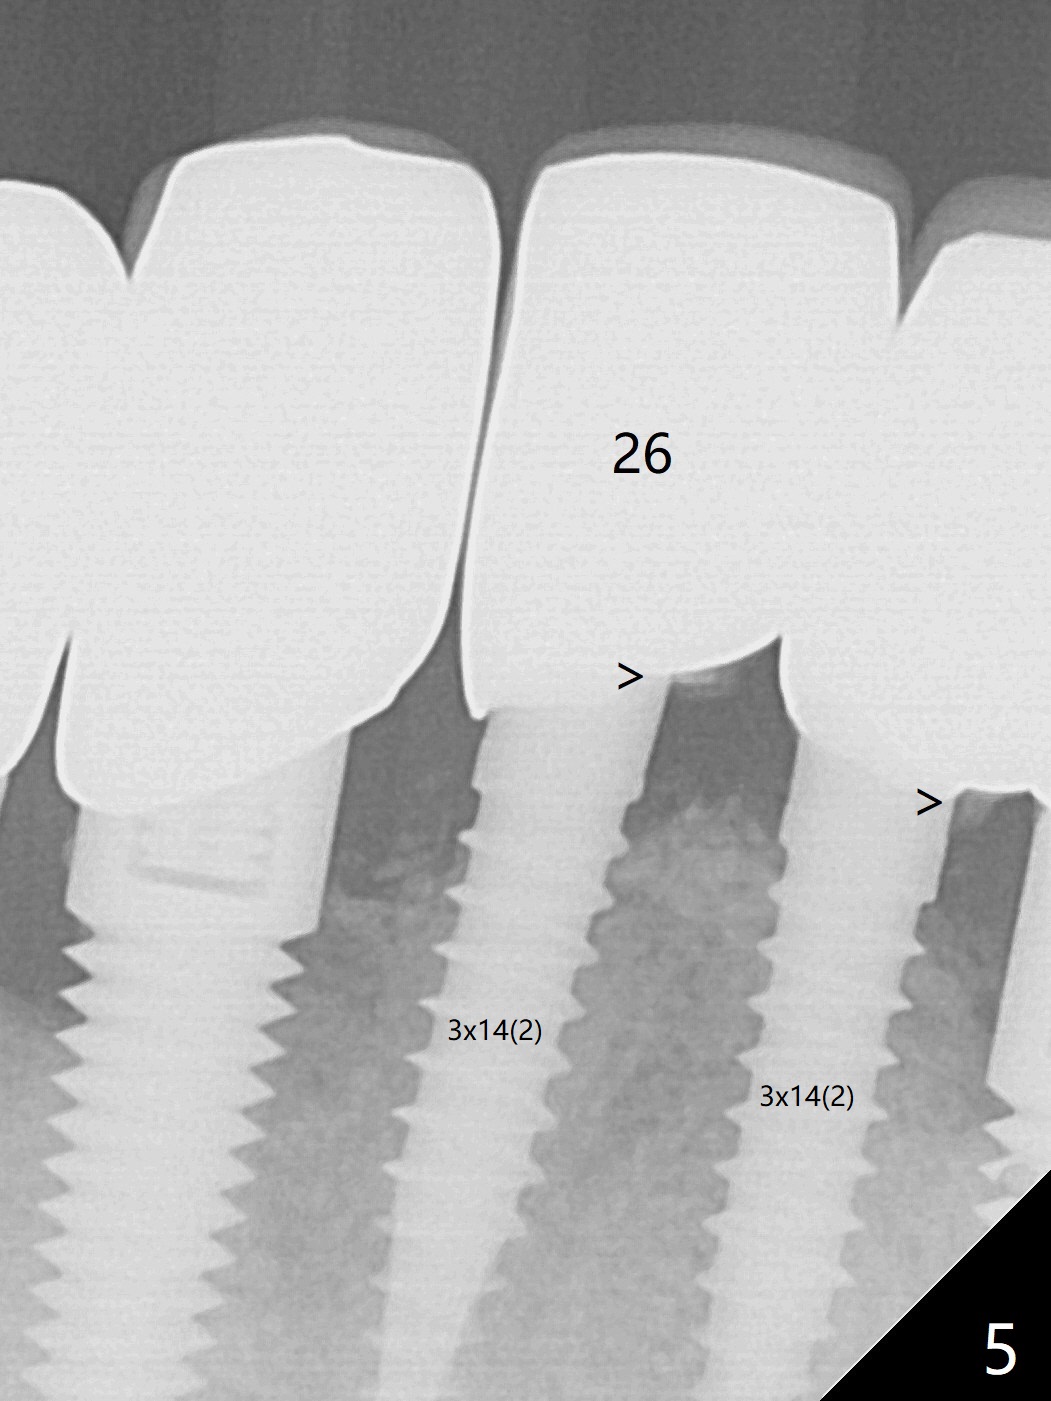

A 67-year-old man with history of chronic periodontitis and bruxism returns to clinic requesting implant for the tooth #20 with mobility (Fig.1). To assure No Deviation of implant placement, Lindamann bur will be used to remove the most coronal of the buccal aspect (Fig.2 *, 3 pink dashed line) of the thick lingual plate (L) during osteotomy. To reduce bone loss (Fig.4 *) associated with residual cement (Fig.4,5 arrowheads) of the tissue-level implants, a bone-level one (SM) will be used at #20. Check whether the nearby implant (#19) has infection clinically and bone graft if needed. Buccolingual threads of the #27 implant are also exposed 3 years 9 months post cementation (Fig.6). An ideal treatment is probably to remove the 4.5x17 mm tissue-level implant and place a 3.8x10 mm bone-level one deeper and a little mesial with bone graft.